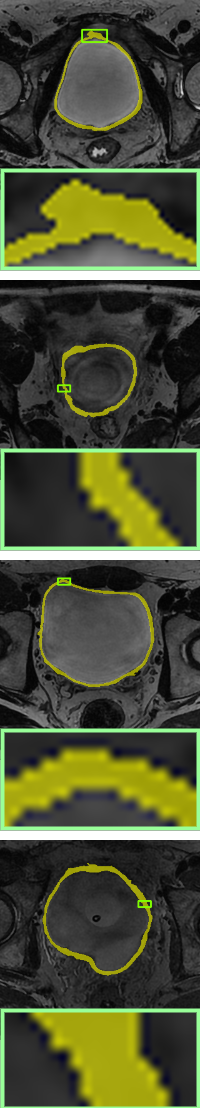

In this section, we will add two different topological energies to Topo-NLSTD model Eq. 13. For convenience, when adding energy without width information Eq. 11, it is denoted as PH; when adding width-aware topological energy Eq. 12, it is denoted as WT. Fig. 7, Fig. 8 and Fig. 9 show the results on synthetic images, the International Symposium on Image Computing and Digital Medicine (ISICDM) 2019 dataset [isicdm] and the Massachusetts Roads dataset [mass], respectively. From the results, we can see that NLSTD retains more image information compared to STD rather than performing a simple smoothing. Then, the results of PH are usually connected to a single-pixel width line or a single-pixel genus to satisfy a given topological constraint. In contrast, our proposed energy not only maintains the topological consistency well, but also fuses the width information.

Image

UNet[unet]

STD[std]

NLSTD[densecrf]

PH[ph]

Proposed WT